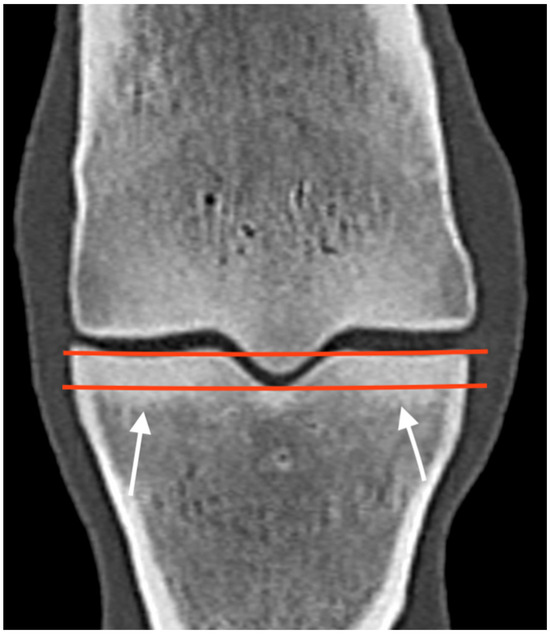

3.1. The Third Metacarpal Bone (McIII)

| Hypoattenuating lesion in the dorsal subchondral bone Subchondral bone thickening Dorsal/palmar half Increased attenuation in the trabecular bone Dorsal/palmar half Cone shaped/patchy Focal separated hyperattenuation | Hyperintense signal in the dorsal subchondral bone Subchondral bone thickening Dorsal/palmar half Decreased signal intensity in the trabecular bone Dorsal/palmar half Cone shaped/patchy Focal separated intermediate/low signal intensity | Radiolucent lesion Subchondral bone thickening Dorsal Increased trabecular bone opacity | |

| Medial/lateral condyle | |||

| Subchondral bone thickening Dorsal/palmar half Increased attenuation in the trabecular bone Dorsal/palmar half Hypoattenuating lesion in the subchondral bone Location | Subchondral bone thickening Dorsal/palmar half Decreased signal intensity in the trabecular bone Dorsal/palmar half Increased signal intensity in the subchondral bone Location | Increased opacity in the trabecular bone Lucent lesion in the subchondral bone Location | |